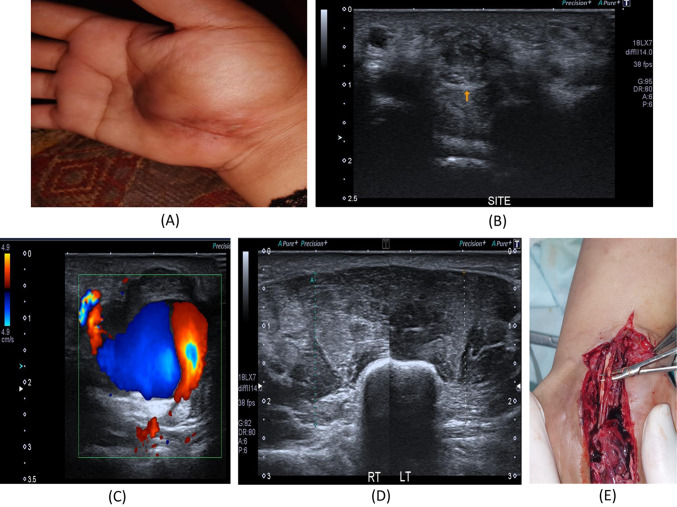

Fig. 2.

26-year- old female with a history of right distal radial fracture in July 2021 treated, After the cast removal, numbness and tingling along the radial aspect of the palm with loss of sensation of the middle finger and newly developed progressive increased thenar swelling. A Patient’s hand with prominent swelling of the thenar eminence and mid-palmar incision scar. B B-mode image, transverse axis, reveals loss of normal sonographic appearance of the left median nerve at the carpal tunnel with related hypoechoic superficial scar tissue, suggesting partial nerve injury. C Color Doppler mode image reveals pseudo-aneurysm; Pepsi sign with an area of luminal thrombosis. D The B-mode image of the thenar muscles, increased echogenicity of the left thenar muscles as compared to the right side with rather preserved girth. E Intraoperative image revealed complete injury of two of the sensory branches of the median nerve